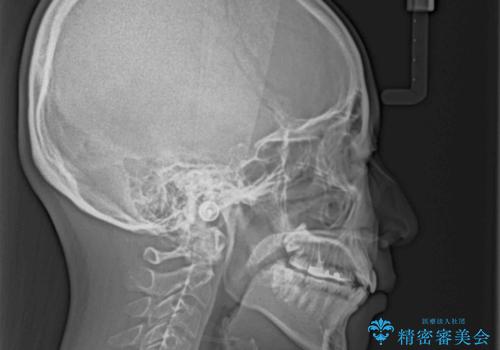

- 八重歯やクロスバイトを気にして来院された患者様です。

口元の突出感はありませんでしたが、デコボコが強く、非抜歯矯正とすると出っ歯仕上がりとなる可能性があったため、上下左右の第一小臼歯4本を抜歯し、ワイヤー装置にて矯正治療を行うこととしました。